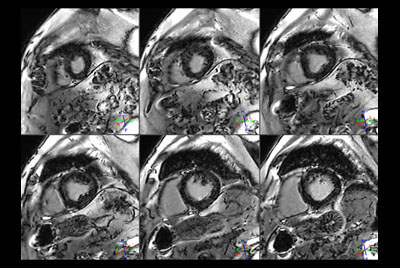

Acute myocardial infarction